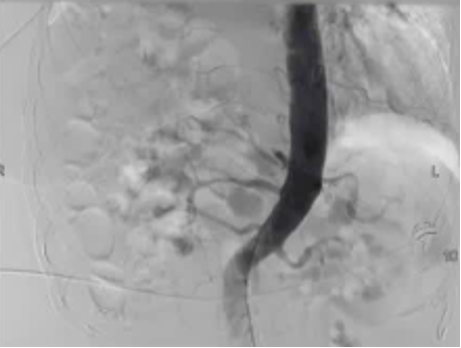

Empiric Embo of Tumor Related GI Bleed

|

Rectal CA |

Met to duodenum |

-

37 angios in 26 patients

Most had findings of tumor

Neo or hyper-vascularity

91% for acute bleeding

50% for chronic bleeding

No ischemic complications

Tandberg - 2012 JVIR 23:1445